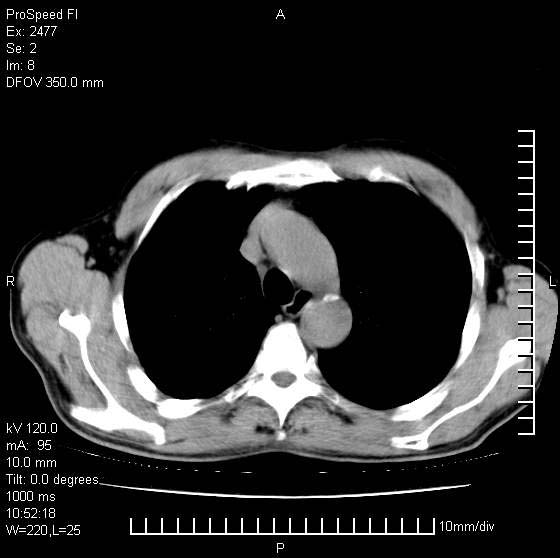

以下是引用天南地北在2007-10-9 14:29:00的发言:[br]1:右上肺结核[br]2:右肺下叶肿块:不支持肺癌,首先考虑炎性病变-肺脓疡可能性大[br]理由:1:临床病史支持,肺脓肿症状不明显应该是不规则服药造成。[br] 2:肿块边缘模糊,周围可见炎性渗出,长毛刺,内见支气管征,不过有点不规则。[br] 我感觉下肺癌这个诊断有点偏左,建议积极抗炎治疗后复查

以下是引用卜一在2007-10-9 15:55:00的发言:[br][br] [br] 1:右上肺结核[br]2:右肺下叶肿块:不支持肺癌,首先考虑炎性病变-肺脓疡可能性大[br]理由:1:临床病史支持,肺脓肿症状不明显应该是不规则服药造成。[br] 2:肿块边缘模糊,周围可见炎性渗出,长毛刺,内见空气支气管征,不过有点不规则。[br] 我感觉下肺癌这个诊断有点偏左,建议积极抗炎治疗后复查![br]支持! [br] [br] [br]

以下是引用wxy7406在2007-10-9 21:02:00的发言:[br]结合临床病史首先考虑感染性病变,但周围型肺癌不能除外,1.患者年龄偏大2.临床有咯血3.(也觉得是最重要的一点)病灶内有偏心性空洞。

以下是引用hhcckk在2007-10-9 15:18:00的发言:[br]右上肺病灶考虑结核,病灶多种形态并存(纤维化、增殖性病灶并存)[br]右下肺病灶比较难说,个人意见更趋向于“天南地北”的诊断----肺脓肿[br]1、病人有明显的寒战,高热,肿瘤病人很少出现[br]2、病灶周围的肺纹理走向柔和,没有肿瘤病灶常见的集束征[br]3、病灶边缘的毛刺较长,恶性肿瘤多为短毛刺[br]痰中血丝和病人的年龄是两个不利于良性肿块的因素,建议早点活检